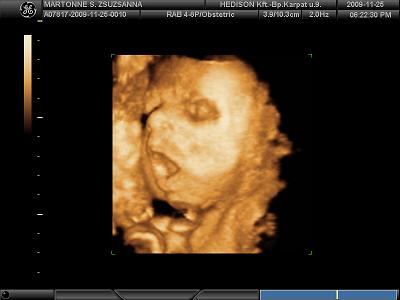

Köszönöm a képeket!!!!!

Tenci jól eltalálta, tényleg Jolie-s szája van Tominak!

És ha még Brad Pittre is fog hasonlítani............!!!!!!!!